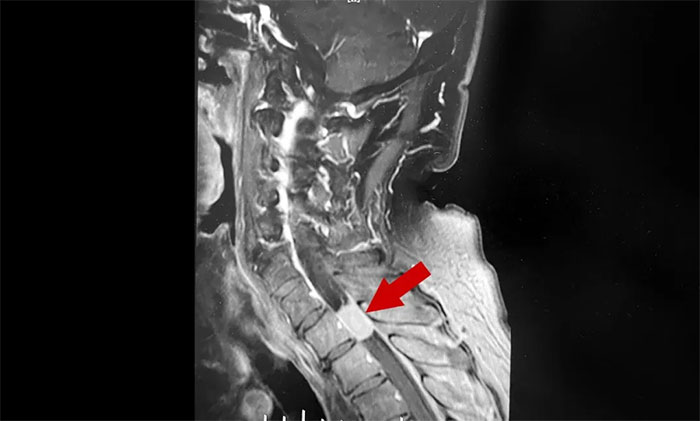

半个月前,陈阿姨发现左手臂麻木感越来越强烈,做家务都有点无力,还出现了胸部麻木和膝盖疼痛,这才在家人的陪同下到当地医院求诊。经颈椎核磁共振检查,结果显示颈髓椎管内肿瘤。困扰陈阿姨多年的上肢麻木不是颈椎病,而是肿瘤所致。

▲ 双手麻木要警惕颈髓椎管内肿瘤